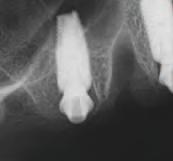

S-a stab l t că este necesar un des gn FP1 al proteze pentru mandbulă, în t mp ce un des gn FP3 se mpunea în cazul max larulu . S-a efectuat o tehn că duală de scanare pentru a captura o mag ne 3D a creste restante folos nd marker

f duc al pe noua setare restaurat vă. Este mportant să se ut l zeze un mater al rad oopac atunc când se capturează poz ț a ex stentă a m n - mplantur lor în cav tatea orală, deoarece acest lucru va perm te folos rea mplantur lor ex stente în spr j nul unu gh daj ch rurg cal 3D pentru plasarea no lor mplantur , dacă poz ț a celor ex stente nu nterferează cu locaț a mplantur lor de nserat.

10. Ghidul chirurgical mandibular a fost creat pentru a fi susținut de mini-implanturile existente.

11. La mandibulă, implanturile au fost plasate fără a interfera cu mini-implanturile existente.

în t mpul etapelor de tratament până la convers a setăr prov zor în proteza ntermed ară med ată înșurubată, deoarece poz ț a lor nu a nterferat cu locaț a ș d str buț a no lor mplantur mand bulare. Însă în cazul arcade max lare, m n - mplantur le trebu au să f e îndepărtate îna nte de nserarea no lor mplantur (f g. 8-10).